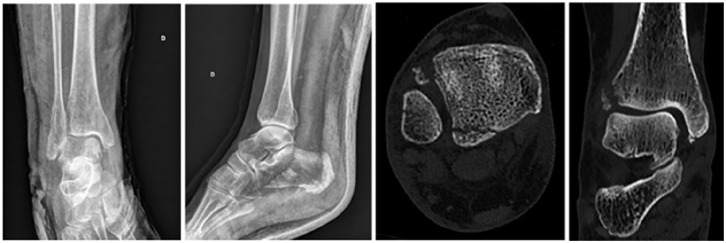

Background: Tillaux-Chaput tubercle fractures in adults often go unnoticed on standard radiographs in the setting of other malleolar fractures. This study aimed to identify clinical and radiologic factors associated with these fractures to develop a decision aid for computed tomographic (CT) diagnosis.

Results: Tillaux-Chaput fractures were undetected on standard radiographs in 60% of cases. In multivariate analysis, only age >60 years and injury mechanisms with Lauge-Hansen pronation-external rotation stage III or IV injuries were found to be highly associated with Tillaux-Chaput tubercle fractures.

Abstract Image